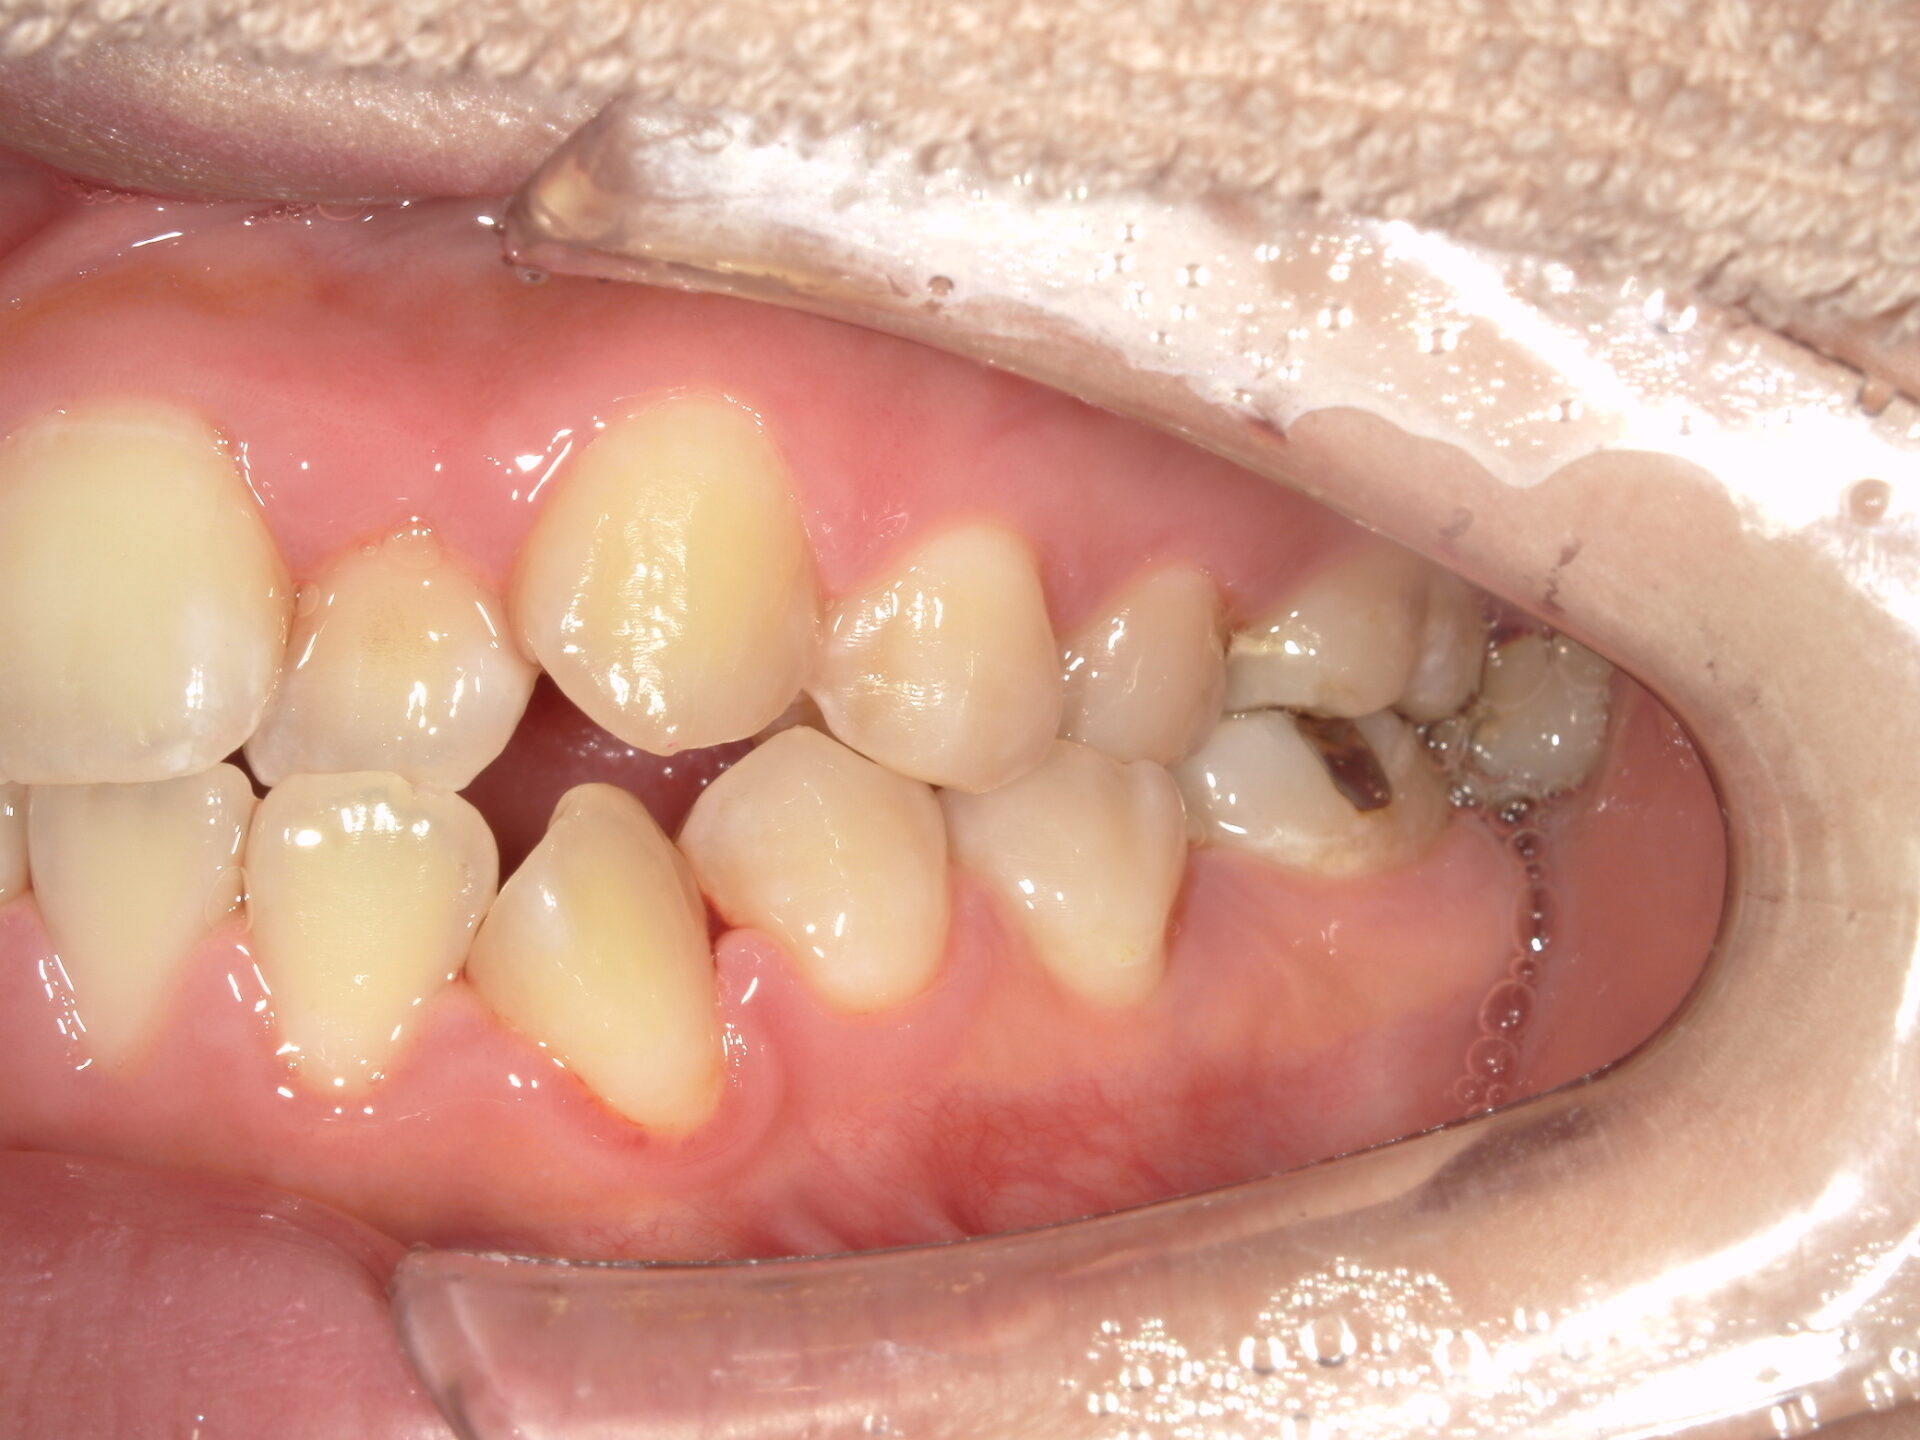

患者さんの年齢 20代 女性 症状 八重歯がコンプレックス、白い歯を入れたい 治療内容 セラミック治療 費用 費用150万(税抜) 治療期間・回数 治療期間1ヶ月・通院回数3回 メリット 治療期間・回数が少ない デメリット・リスク 術後知覚過敏が起こる事ある - セラミック治療

before

after